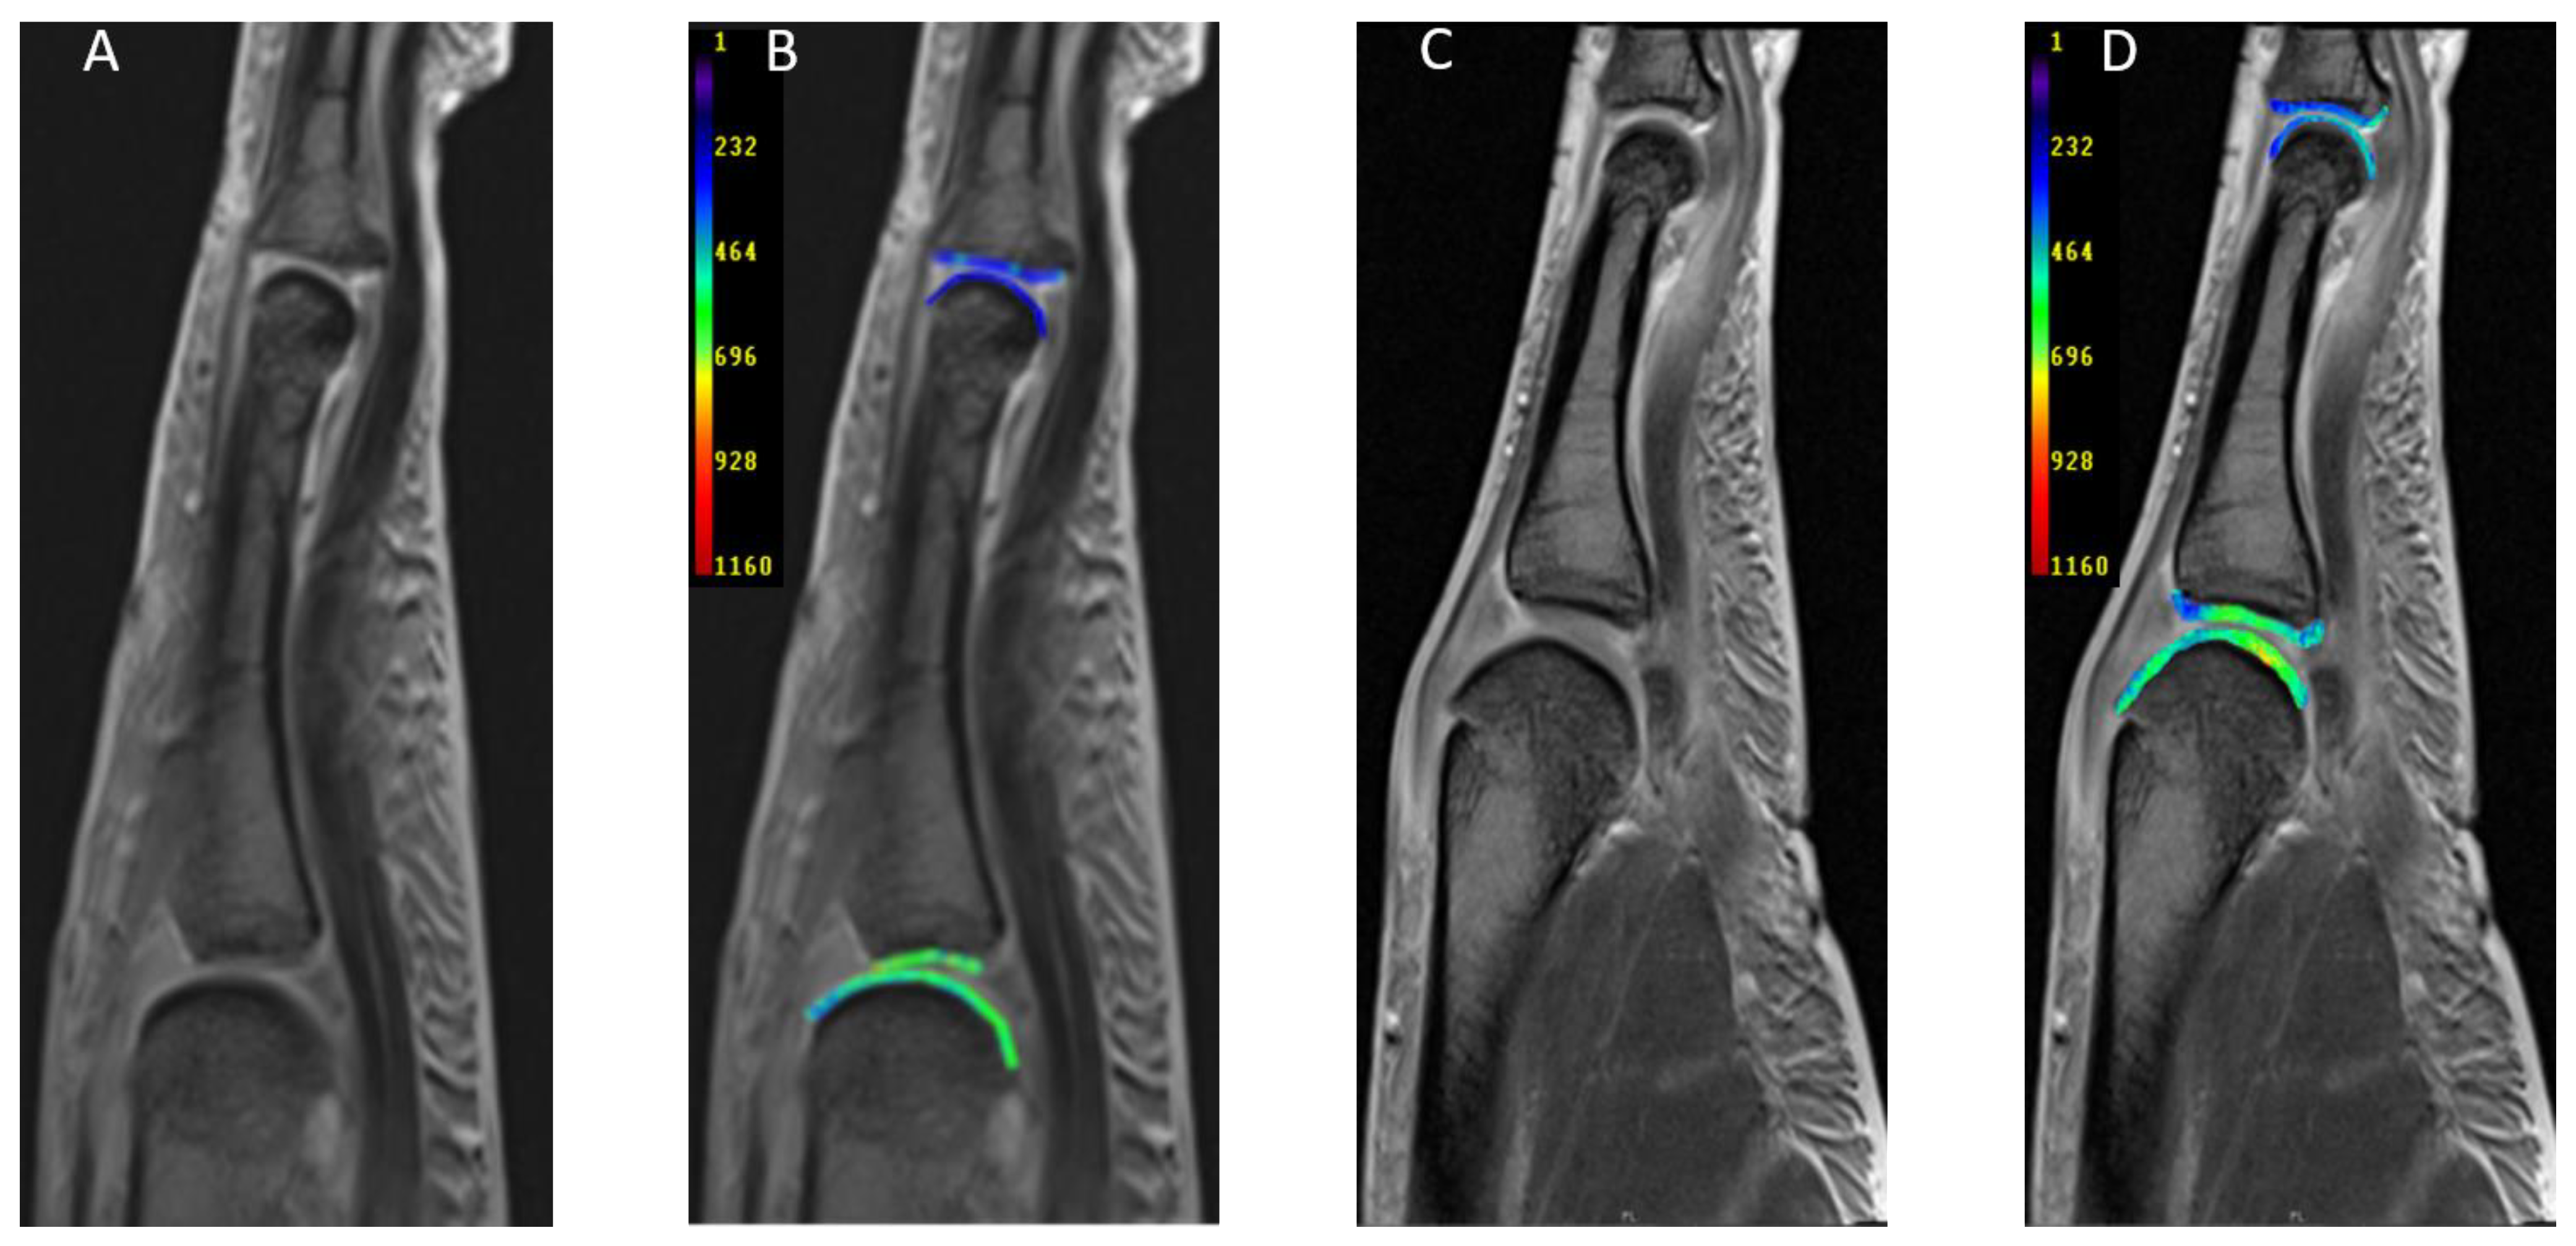

DGEMRIC in the Assessment of Pre-Morphological Cartilage Degeneration in Rheumatic Disease: Rheumatoid Arthritis vs. Psoriatic Arthritis